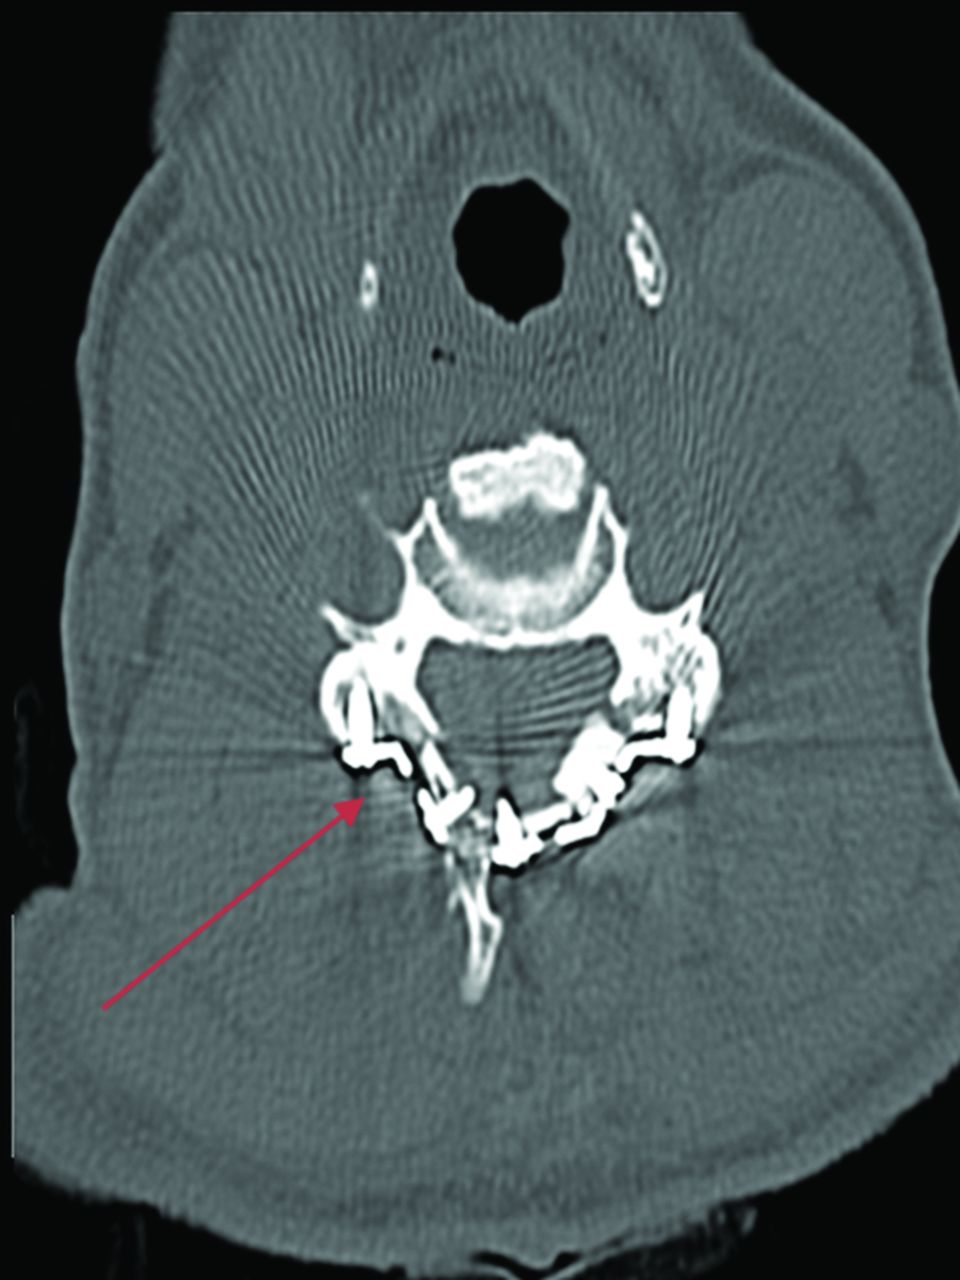

Fracture-negative, radiologist true-negative, CNN false-positive case example. Axial cervical spine CT image demonstrates a postsurgical defect involving the right lamina secondary to laminoplasty. Red arrow demarcates postsurgical defect. This case example illustrates a drawback of the algorithm to fail to differentiate postsurgical changes from fractures.